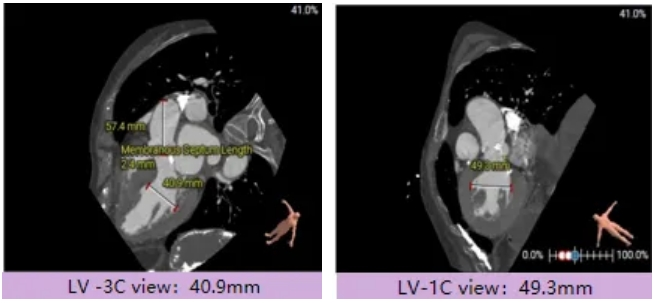

宋光远教授 首都医科大学附属北京安贞医院(点击查看专家详细简历) 技术革新不止,创新求索不辍:一切从患者出发,不断追求创新是内心的坚定。当年‘ALL IN ONE’的探索,正是怀揣着这份初心 —— 通过整合器械与操作,将入路创伤缩至最小,让患者在微创中更快康复,这是技术对患者的温柔承诺。而术中脑保护,是我们为安全筑牢的另一道防线。 此次预装干瓣的临床应用,让我们直面瓣膜“耐久性“临床困境,期待创新技术助力全生命周期管理! 病例概览 患者病史 患者因 “劳力性呼吸困难半年余,加重 20 天” 入院。高血压病史 20 年,最高血压 160/110mmHg;高脂血症病史;反流性食管炎。 超声提示:主动脉流速 Vmax 4.66 m/s,平均压差 53mmHg,左室射血分数(LVEF)40%; 超声诊断:主动脉瓣狭窄(重度)、主动脉瓣反流(轻中度)、二尖瓣狭窄(轻度)、二尖瓣反流(轻度)、三尖瓣反流(轻中度)、左房增大,左室肥厚。 术前CT 瓣环(Annulus)直径:22.9mm,左室流出道(LVOT)直径:周长径 23.8mm;总钙化负荷1239mm³(HU850),钙化集中于无冠窦,且蔓延至 LVOT,呈重度钙化表现;LVOT-Annulus 呈微直筒型,瓣上限制较重。左冠脉开口高度略低,瓣叶不长、窦部空间较大,结合钙化分部情况,预估双侧冠脉遮挡风险较低。室间隔膜部较短(2.4mm)有一定PPI风险,心室大小可,心脏角度64°,升主长度短于胶囊腔长度,同轴有一定困难。 · 造影角度及入路情况:主动脉弓角度可,但降主动脉折曲明显,双侧髂股动脉存在粥样硬化。 手术策略 采用 “极简式” 手术方案:18/20mm 球囊预扩张,植入金仕生物 Prostyle-A 预装干瓣(AV 26),配合长鞘,同时植入脑保护装置以降低卒中风险。 手术过程 球囊预扩:18号球囊预扩 输送系统顺利过弓跨瓣: 瓣膜植入:工作位观察位置适宜,完成植入。 术后即刻:术后造影显示瓣膜位置佳 入路与血管:撤出大鞘后检查,降主动脉仍存在较大弯折;入路闭合良好,无明显出血或血管并发症。 Prostyle A®预装干瓣——助力临床最优化解决方案: √ Mircro-EX™专利抗钙化技术:极简式预装干瓣,不使用戊二醛浸泡,减少钙化成因,干态存储的瓣膜术中无需清洗瓣膜,减少组装步骤,缩短手术时间,尤其适合复杂病例中的高效操作; √ 平衡的径向支撑力:重度钙化的患者,形态展开良好,在横位心等复杂情况下实现稳定锚定及释放; 专家简介 苑飞 首都医科大学附属北京安贞医院(点击查看专家详细简历) 姚晶 首都医科大学附属北京安贞医院(点击查看专家详细简历) · END ·